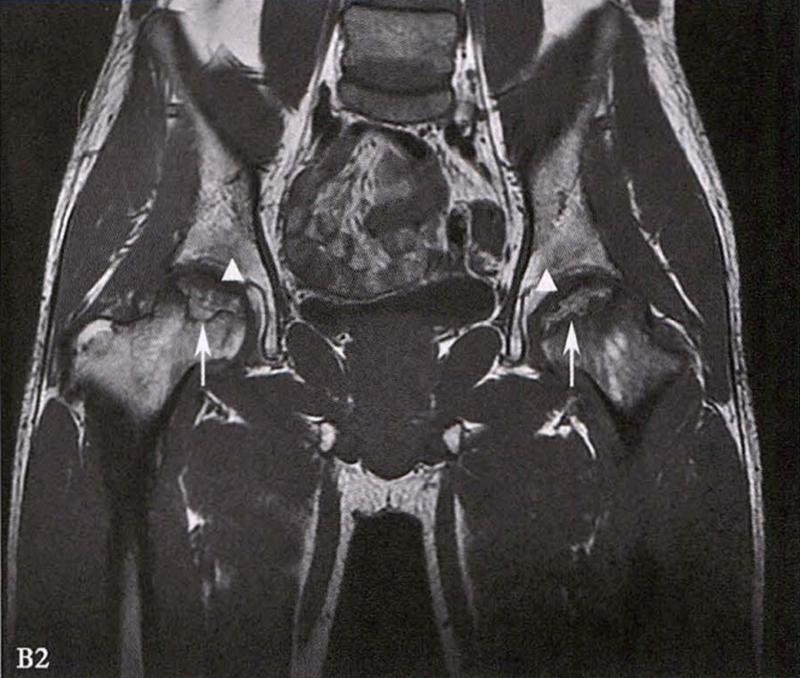

B.男性,31岁,双侧股骨头坏死,双侧均为Ⅲ期。X线片示双侧股骨头密度不均、股骨头稍变扁(B1)。MRI(T1加权像)示股骨头内多发不规则信号带(B2),股骨头内凸向大转子的双线征(白色箭)和软骨下骨骨折(白色三角)。